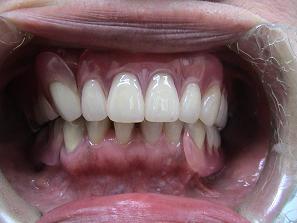

バネなし入れ歯を入れた

状態です!!

* 金属のバネがないので

見栄えが良いです!

入れ歯が入っているとは

気がつかれにくいです!!